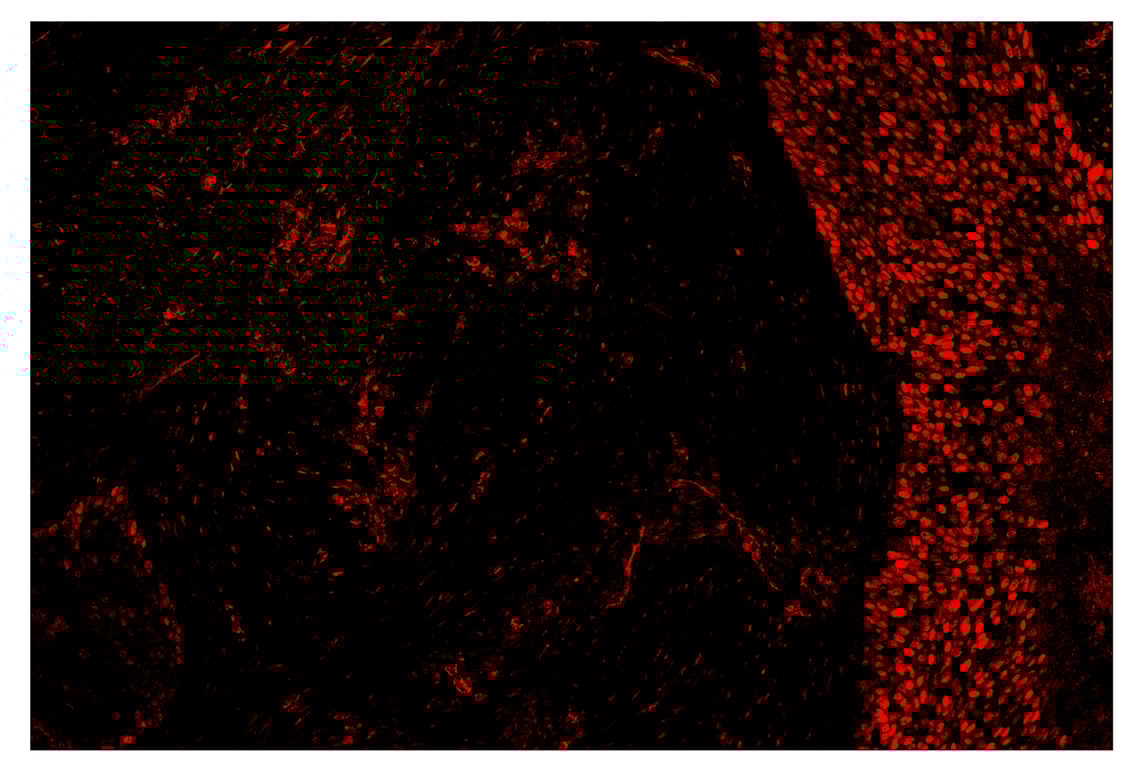

SignalStar™ multiplex immunohistochemical analysis of paraffin-embedded human gastric adenocarcinoma using Phospho-Stat3 (Tyr705) (D3A7) & CO-0029-594 SignalStar™ Oligo-Antibody Pair #86323 (left, yellow) and ProLong Gold Antifade Reagent with DAPI #8961 (left, blue) compared to chromogenic immunohistochemical analysis of a serial section of paraffin-embedded human gastric adenocarcinoma using Phospho-Stat3 (Tyr705) (D3A7) XP® Rabbit mAb #9145 (right). All fluorophores have been assigned a pseudocolor, as indicated. Staining was performed on the BOND RX by Leica Biosystems.

Immunohistochemistry Image 5: Phospho-Stat3 (Tyr705) (D3A7) & CO-0029-488 SignalStar<sup>™</sup> Oligo-Antibody Pair